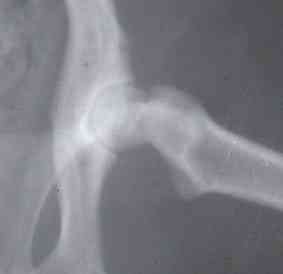

De las muchas enfermedades que un animal puede tener, la artrosis, como se la conoce también en los humanos, puede ser una de ellas, una enfermedad degenerativa de las articulaciones que se produce por el desgaste del cartílago articular y el hueso. Esto lo que hace es que se produzca dolor porque, al no tener esa especie de almohadilla entre el hueso, al rasparse, se da dolor.

La artrosis es muy común en los perros y puede darse por traumatismos, infecciones, enfermedades del sistema inmune, enfermedades del desarrollo o por evolución de una displasia de cadera o codo, etc.